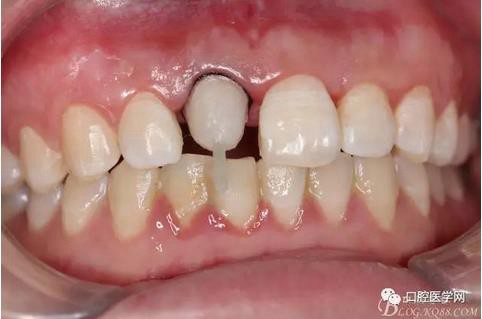

術(shù)前原有牙冠復(fù)位,牙齦紅腫。